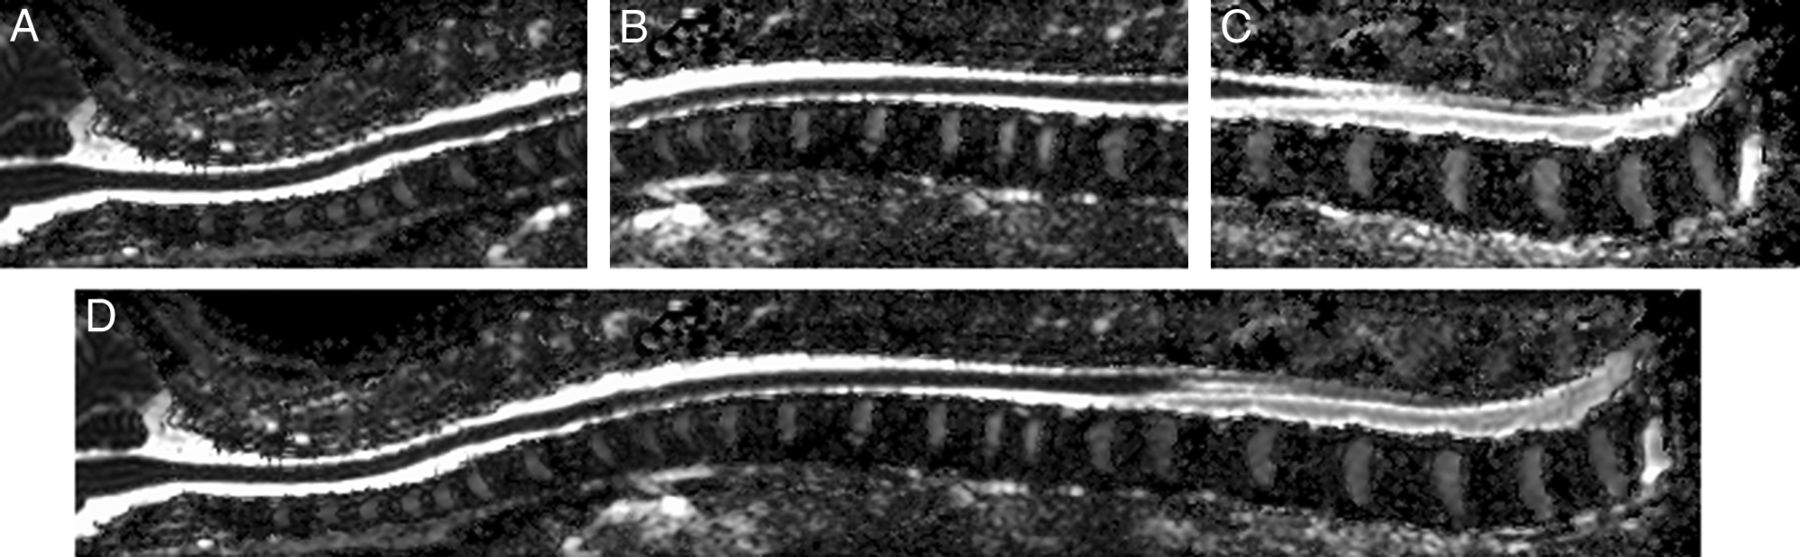

A 15-channel sensitivity encoding spine coil was used to scan the spinal cord for each subject. Conventional T2-weighted images were acquired with a turbo spin-echo sequence with the following parameters: TR = 4048 ms, TE = 120 ms, flip angle = 90°, NEX = 2. Spinal cord DTI was acquired at the upper, middle, and lower parts with sufficient overlapping areas. Figures 1A–C show an example of these 3 parts. In each part, sagittal sections parallel to the long axis of the subject's body were acquired to cover the whole spinal cord. Thirty sagittal sections were collected for the healthy girls in each part. Due to the curves of spinal cord in AIS, an equal or larger number of sagittal sections, ranging from 30 to 40, were required to capture the entire spinal cord. Spinal cord DTI was performed by using the single-shot EPI sequence with the following parameters: TR = 8180 ms, TE = 63 ms, FOV = 130 × 219 mm2, flip angle = 90°, NEX = 6, matrix = 64 × 110, section thickness = 2 mm, gap = 2 mm. After reconstruction, images were zero-padded and interpolated to 224 × 224 with voxel size of 0.98 × 0.98 × 2 mm3. Six directions of diffusion gradients with a b-value of 500 s/mm2 and 1 B0 volume were collected. The number of gradients was reduced compared with the brain DTI because of time constrains because DTI acquisition of the whole spinal cord required 3 separate sessions. Together with the morphologic T2-weighted sequences, the total scanning time of the spinal cord was 30 minutes or longer if the scoliosis curve was severe. The scanning time was, therefore, kept to a minimum to avoid motion artifacts and discomfort of the subject while image quality was acceptable for analysis.

Sagittal mean diffusivity images show an example of spinal cord DTI stitching. Upper part (A), middle part (B), lower part (C), and stitched (D) spinal cord DTI of the whole spinal cord.

For each subject, diffusion tensor images of the spinal cord were adjacently stitched together to produce the DTI of the entire spinal cord.22 In brief, the adjacent diffusion tensor images were first aligned by using a feature-based registration algorithm. All the images were then warped to the same space and were stitched together by using an effective feathering approach with the Log-Euclidean metrics. The FA and MD scalar maps were visualized to evaluate the effectiveness of the stitching results. Figure 1 shows an MD map of the stitched spinal cord DTI from 1 healthy subject.